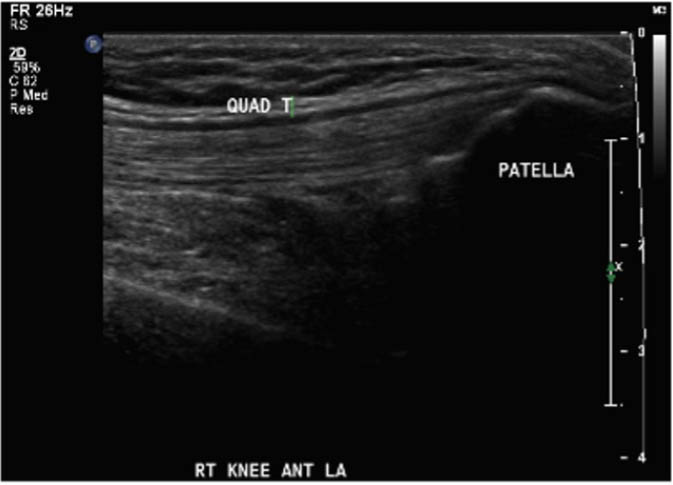

The study procedure consisted of a POCUS performed by a physiotherapist and a sonographer. The POCUS scanning procedure is presented in Appendix 1. The POCUS scans were performed in the haemophilia ambulatory clinic at patient presentation, one-week follow up, and two-week follow-up. The order of assessment was based on clinician availability. The sonographer was allowed to add additional images to the imaging protocol given their area of expertise, but the physiotherapist was instructed to acquire the images according to the scanning procedure. Ambiguous results were referred to the diagnostic imaging department for further formal investigation. Both the physiotherapist and the sonographer were blinded to each other's findings and to the results of previous scans. Methods of blinding included the use of a private clinic room and each clinician performing their assessment and documentation independently. Case report forms were placed in a sealed envelope. POCUS images were saved on the hard drive of the POCUS machine (GE Logiq) using an anonymous participant identification number.

Outcomes were assessed at presentation, one-week follow-up, and two-week follow up, resulting in a three-week study period. For the primary objective, the outcome of interest was the binary decision on the presence or absence of blood within the joint. As the technique and protocol in this study was specific to haemophilia, the criteria used to distinguish blood from effusion on ultrasound was blood presents as a complex fluid collection with mixed echogenicity and displaceable speckles on real time compression and effusion presents as simple anechoic fluid with the absence of echoes [35]. In the context of haemophilia with no symptoms suggestive of infection, complex effusions with mixed echogenicity can be assumed to represent haemarthrosis based on previous studies that have documented the accuracy of this approach using joint aspiration [35]. The physiotherapist completed the scanning protocol and interpreted the findings to make the binary assessment. Since interpreting ultrasound falls outside the scope of the sonographer, the sonographer provided an impression on the presence or absence of blood on the case report form. The radiologist read the sonographer images and provided a final diagnosis. The radiologist also reviewed the images of the physiotherapist performed ultrasound. To compare the level of agreement, the radiologist's final diagnosis was compared to the physiotherapist's interpretation. Both the physiotherapist and the sonographer recorded inconclusive ultrasound findings as absence of blood within the joint.

For the secondary objective, criteria used to evaluate image quality were appropriate pre-sets, depth, field of view, focus, gains/time gain compensation, colour and/or power Doppler, with suitable landmarks and annotation. Image quality was evaluated by the radiologist post hoc and rated as optimal, acceptable, or sub-optimal. Optimal was defined as good image quality with optimal ultrasound settings and correct annotation/documentation. Acceptable was defined as good image quality, with one image setting that should have been better optimized or a minor error in annotation/documentation that did not impact the interpretation of the POCUS scan. Sub-optimal was defined as poor image quality with more than one image setting not sufficiently optimised or an error in annotation/documentation that impacted the radiologists’ interpretation of the POCUS scan.

Post hoc analysis of the quality of the ultrasound images is shown in Table 2. The physiotherapist-performed POCUS scans demonstrated that 84.6% of the images were rated by the radiologist as optimal, 15.4% were rated as acceptable, and none were rated as sub-optimal. For the sonographer-performed POCUS scans, 88.9% of the images were rated as optimal, 11.1% were rated as acceptable, and none of the scans were rated as sub-optimal.